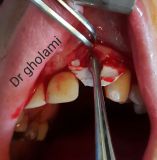

معرفی سیستم SPI همراه با جراحی زنده و Immediate Loading - آبان ۹۵

جراح وسخنران : استاد دکتر غلامعلی غلامی